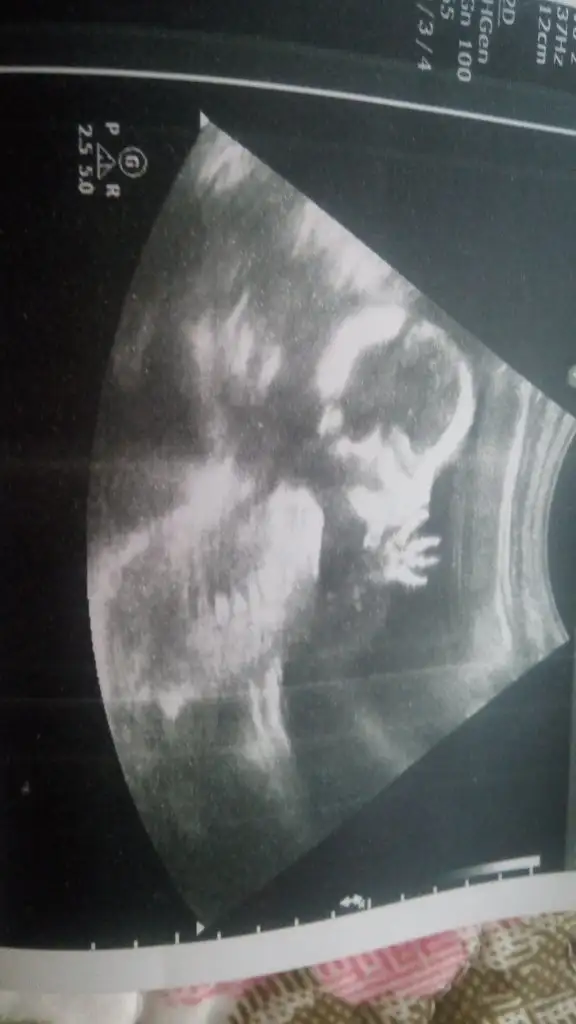

IMG_20150307_120154.webp buda yeni kiza benziyor bacak arazi bos dendi nedir sizce

Eki Görüntüle 1444512 teyzesi bu yeni resmimiz elini emiyo ters attim ama çok merak ediyorum en son kiz dedi ayrintilida kesin ÖĞRENİRSİN dedi ama catliyorum bacak aradinda birşey göremedi 17 haftalık erkekle bebek organi artik belli edwrmi